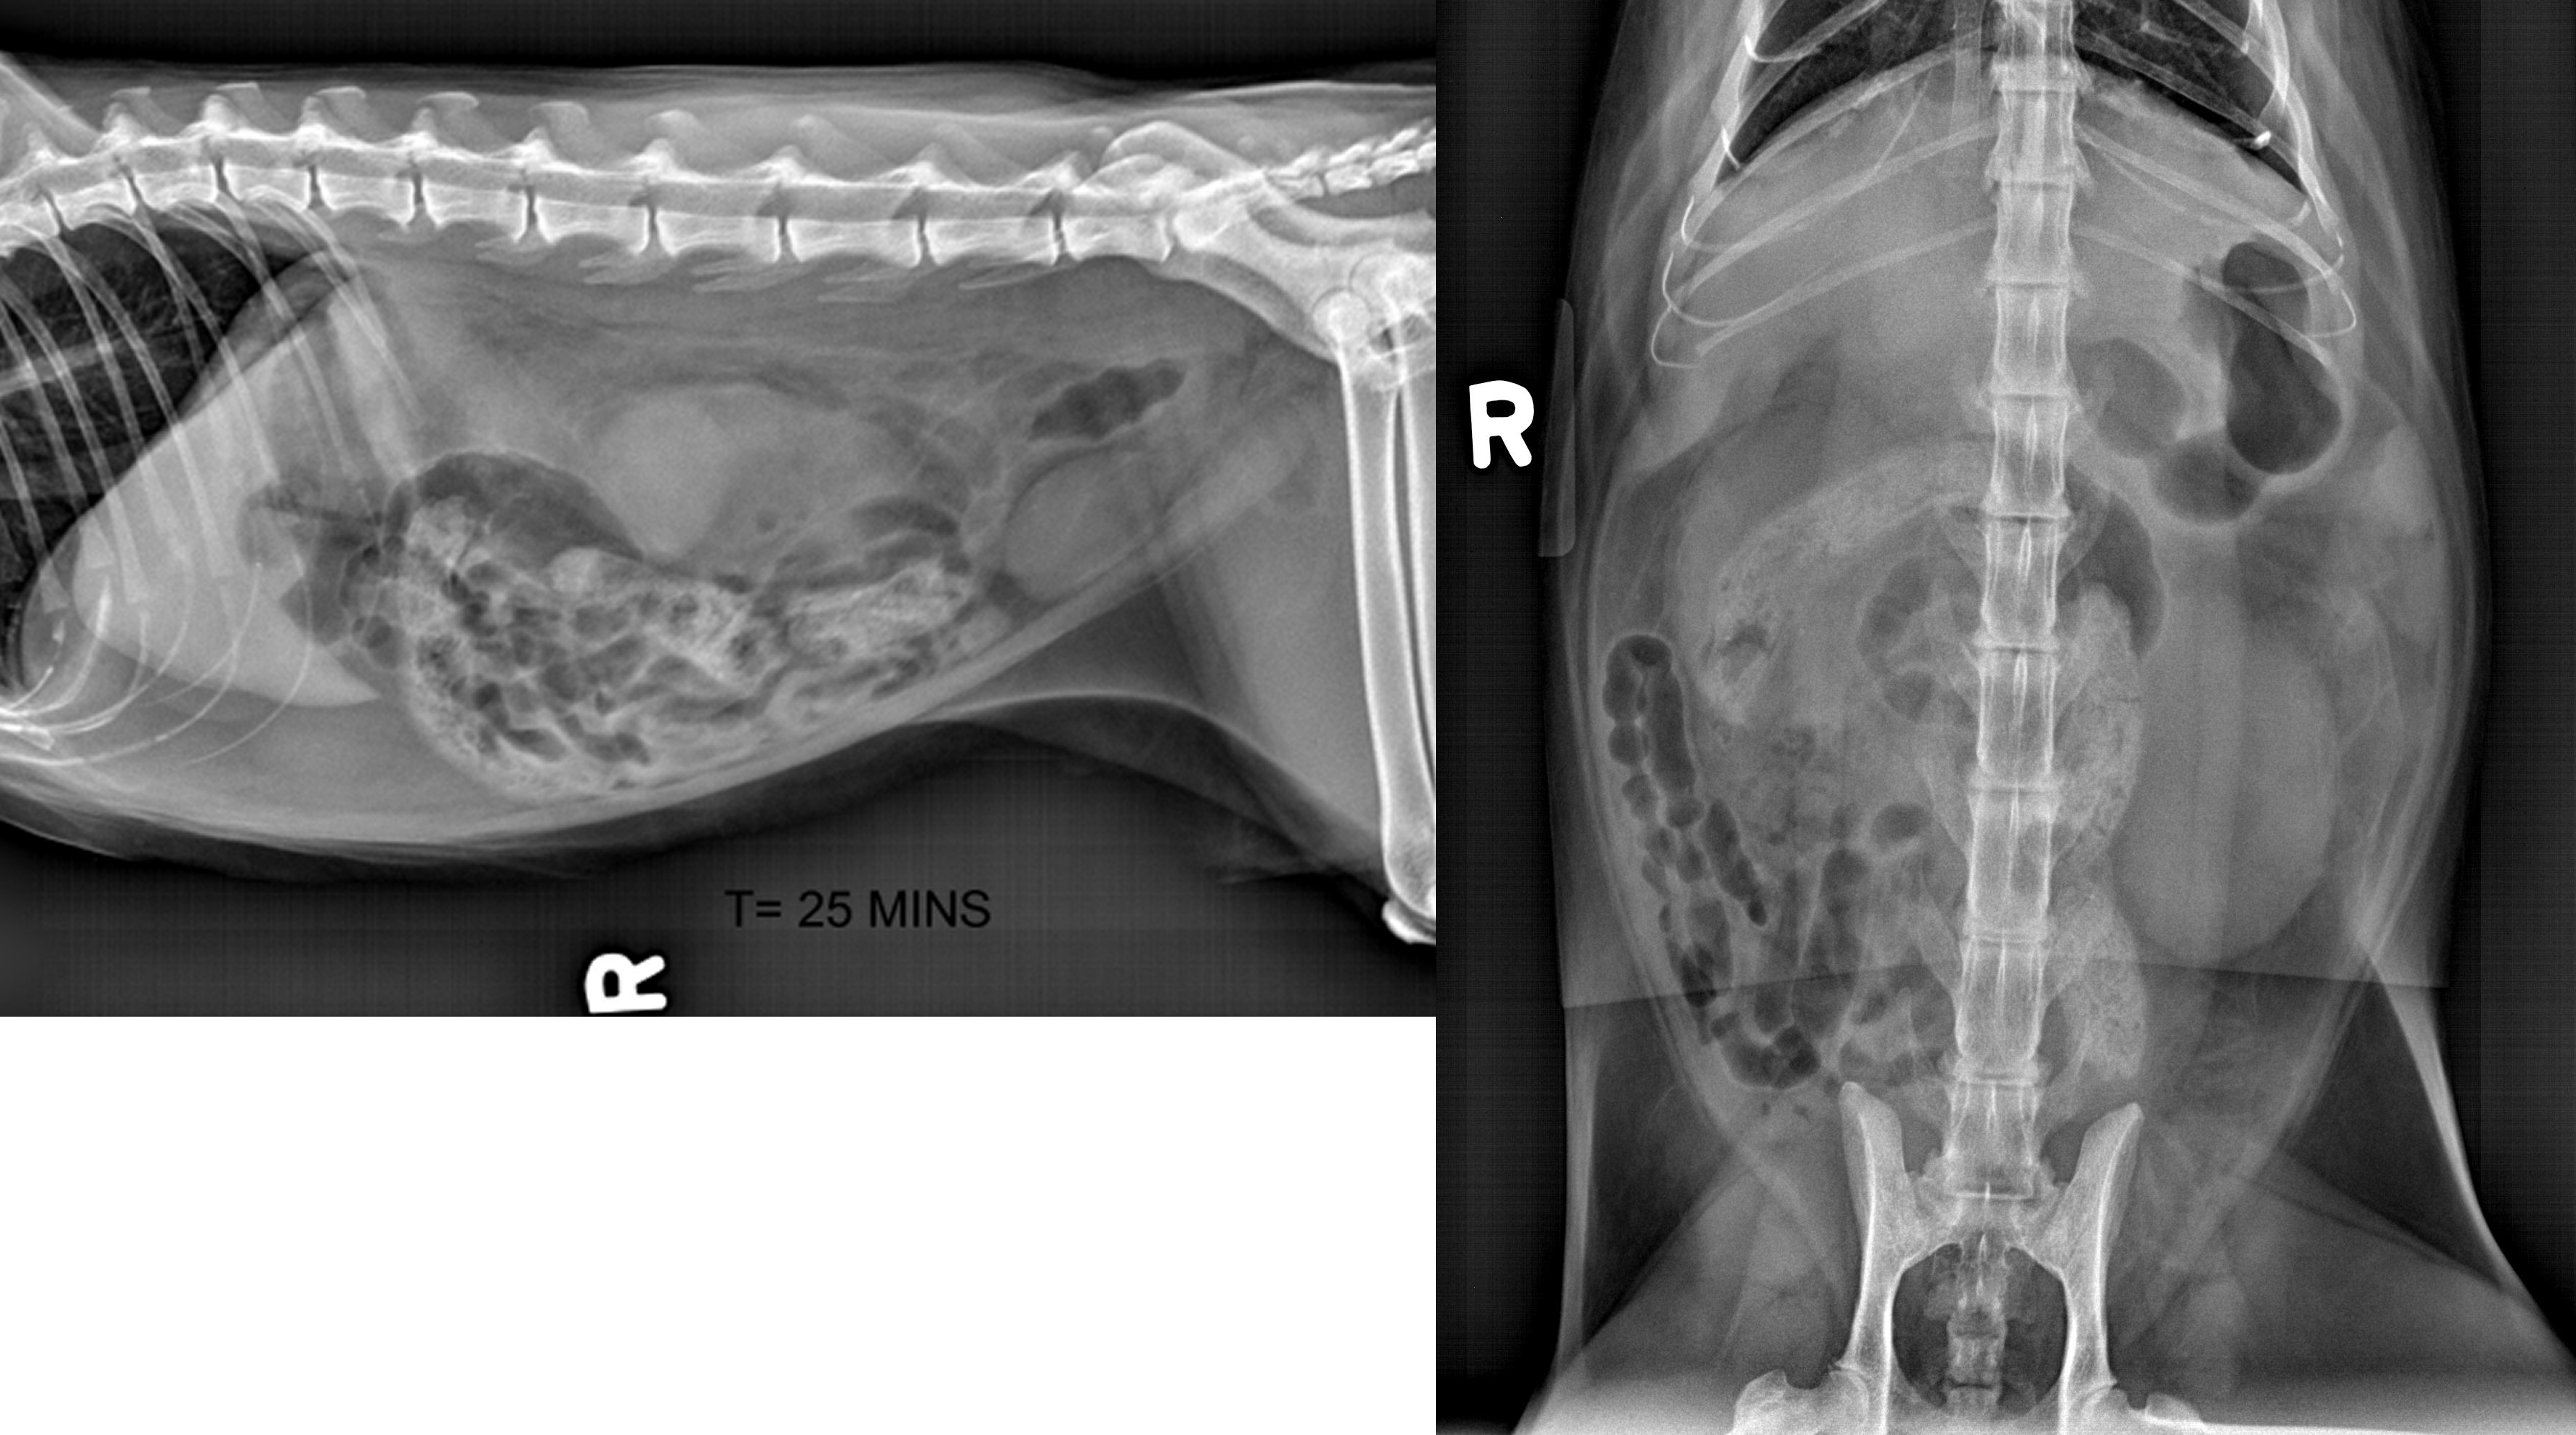

Xray of a Cat Diagnosed with Poisoning and Kidney Failure Stock Photo Kidney Size Cat X Ray The kidneys should be symmetrical in size and shape (oval to. The cat is approximately 7% to 8% dehydrated, mildly depressed, and has a thin body condition and a temperature of 104˚f. The widely accepted normal ultrasonographic measurement for kidneys in a cat varies between 3 and 4.3 cm in length. Ultrasound is a useful imaging tool to assess the. Kidney Size Cat X Ray.

Xray of a Cat Diagnosed with Poisoning and Kidney Failure Stock Image Kidney Size Cat X Ray In some cats, the right kidney may be slightly longer than the left, but the two kidneys. Ultrasound is a useful imaging tool to assess the kidneys in cats, providing an exhaustive evaluation of the size, shape, and renal. The kidneys should be symmetrical in size and shape (oval to. The cat is approximately 7% to 8% dehydrated, mildly depressed,. Kidney Size Cat X Ray.